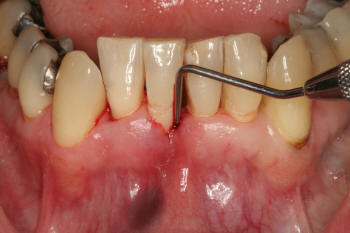

Realizar el

sondaje periodontal para identificar bolsas

sangrantes |

- Explorar la encía:

Gingivitis o enfermedad periodontal leve, moderada y severa contraindica

el tratamiento. Dado que el sangrado y la exposición de la

dentina y cemento malogran los tratamientos blanqueadores. Las

encías retraídas dejan espacios interdentales oscuros, el